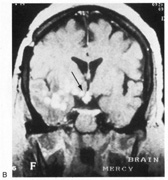

Most striate lesions are infarction, mainly from posterior cerebral artery occlusion (Fig. 14), with sudden onset visual loss and sometimes headache.53 In about half, the visual field defect is the only deficit,53 but in others damage to medial occipito-temporal regions causes amnesia, prosopagnosia, and color perception defects. A syndrome of agitated delirium and hemianopia occurs with lesions of the medial occipital lobe, parahippocampus, and hippocampus.54–56 Brainstem signs include impaired level of consciousness, III nerve palsy, dysarthria and hemiplegia.53 Causes of ischemia are most frequently cardiac emboli and vertebrobasilar occlusive disease; migraine is a rare cause of permanent defects.53 Hemorrhage, vascular malformations, primary and secondary malignancies are much less common.33

Fig. 14. Location and etiology of homonymous hemianopia in 140 patients. (From Fujino T, Kigazawa K, Yamada R: Homonymous hemianopia. A retrospective study of 140 cases. J Neuroophthalmol 6:17, 1986, Aeolus Press, with permission.)